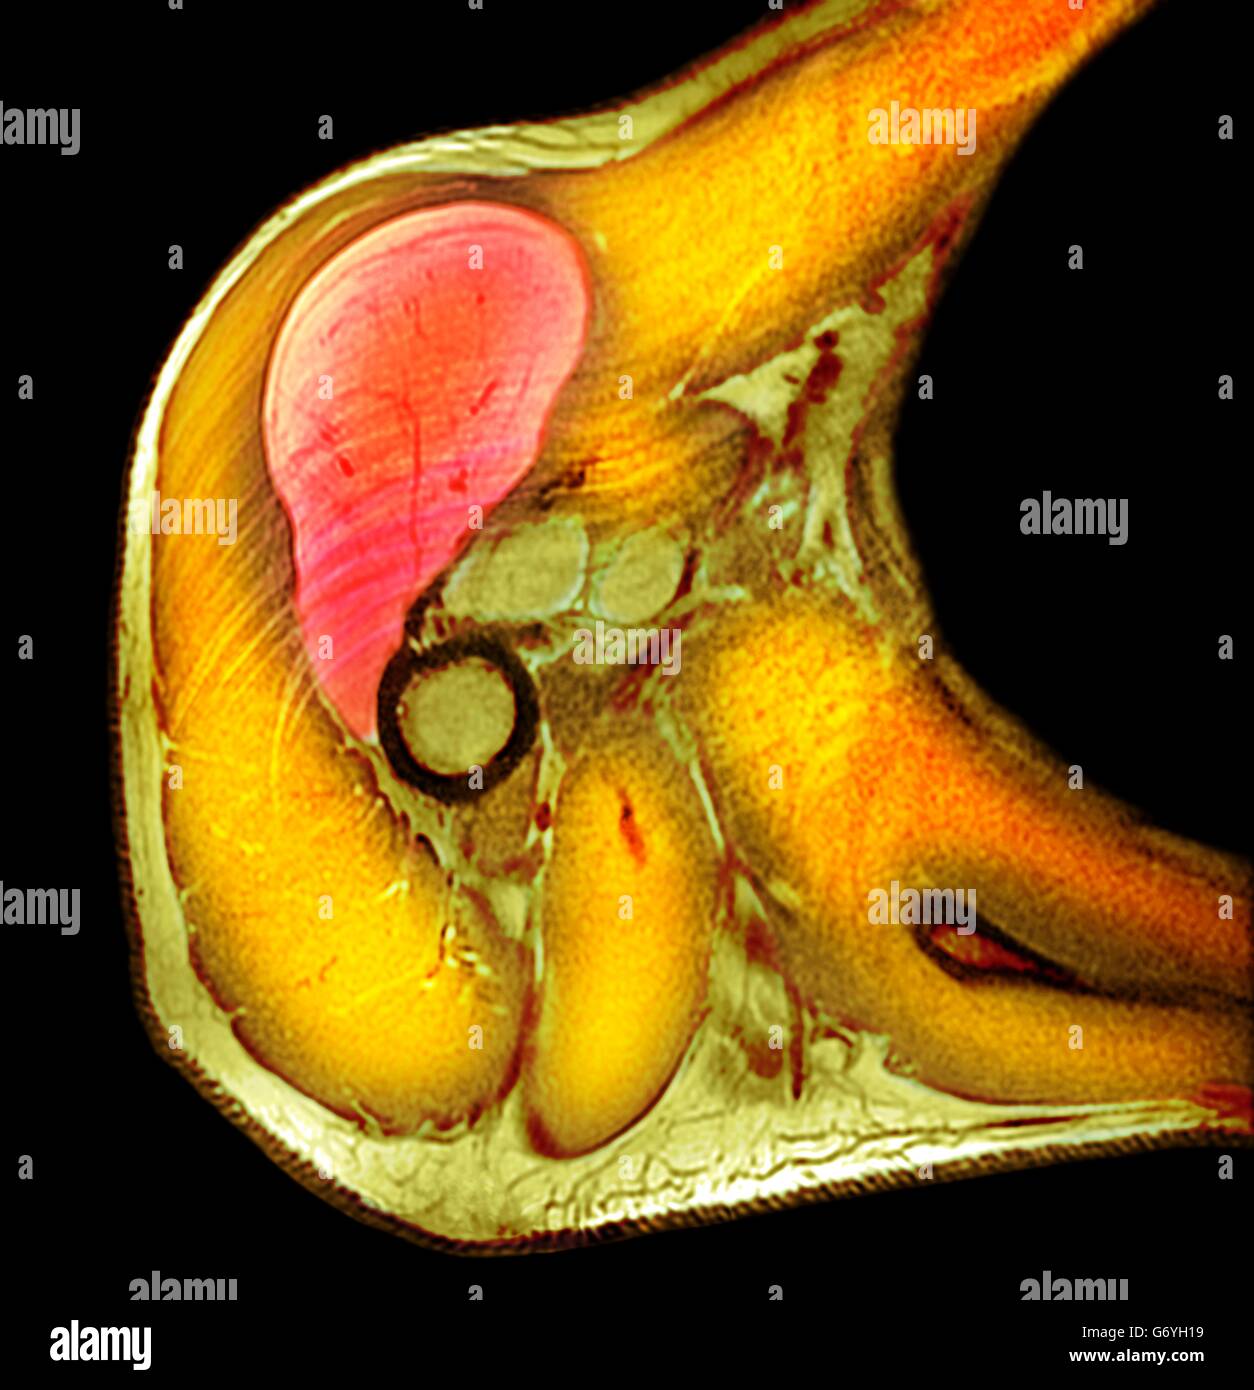

Lipoma | Radiology Key

Lipoma | Radiology Key

Lipoma | Radiology Key

Figure 5 from Tumours of the foot and ankle. | Semantic Scholar